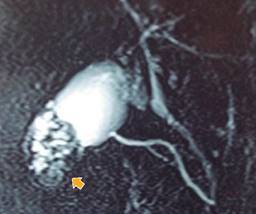

La RMN puede aportar mayor precisión en caso de duda diagnóstica (Figura 2). De hecho, tiene una mayor sensibilidad (73 vs 80.3%) y especificidad (96.3 vs 98.2%) que la ecografía.16 En ella, el engrosamiento de la pared de la VB se puede evidenciar tanto en T1 como en T2. Los senos de RA típicamente aparecen hiperintensos en T2, hipointensos en T1 y no muestran realce de contraste. La conjunción de engrosamiento parietal y divertículos intramurales con el “signo del collar de perlas” distingue la ADM de otras etiologías y se observa en T2 como múltiples cavidades de alta intensidad en la pared vesicular. Este signo es más prominente en la colangio-RMN.21,22

Figura 2: Colangio-RMN. Vista de una adenomiomatosis segmentaria fúndica. Se observa engrosamiento parietal con focos hipercaptantes en el fondo. En T2 se pueden visualizar los senos de Rokitansky-Aschoff (flecha) que permiten diferenciar la hiperplasia adenomiomatosa del carcinoma vesicular.